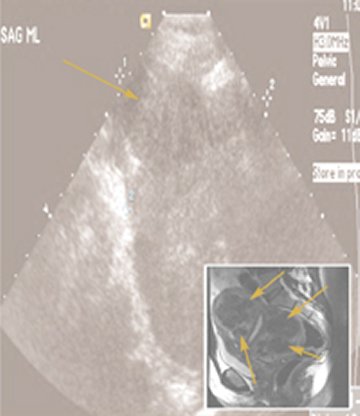

Baird’s team contacted 1,364 black and white women ages 35 to 49 who were members of a health insurance plan in Washington, D.C. Through interviews, medical records, and ultrasound scans, the researchers determined which of the women had at least one fibroid and how large the tumors were. Ultrasound can identify fibroids even if they don’t cause symptoms and might escape a physician’s notice during a routine exam.

In the short term, she says, doctors may develop ways to stop new fibroids from causing problems. With ultrasound tests, it’s already possible to spot fibroids when they’re small, but doctors still can’t do much to neutralize them, short of invasive treatments.

To avoid fertility problems, finding small fibroids may be more imperative than finding larger ones. Baird, Hartmann, and their colleagues recently used ultrasound to detect fibroids among some 1,600 women who had recently become pregnant. The researchers pinpointed the location and determined the size of each fibroid they found and then followed the women to see which ones had successful pregnancies.

Fibroids that jut into the uterine cavity increase the risk of spontaneous abortion, the researchers found. By altering the inner contours of the uterus, those tumors may interfere with the growth of the fetus, the team speculates.

However, many fibroids grow embedded in the uterine muscle and don’t project into the uterine space. In the muscle, fibroids with diameters smaller than 3 cm increase miscarriage risk, Hartmann and her colleagues reported in Houston last March at the annual meeting of the Society of Gynecologic Investigation. In contrast, Hartmann says, larger fibroids don’t.